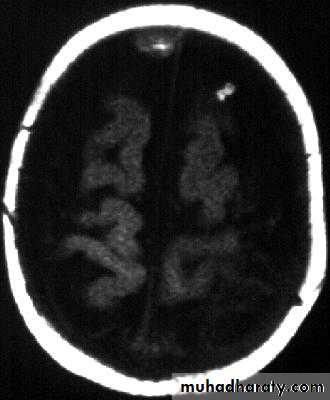

Bacterial Meningitis with cerebral oedema